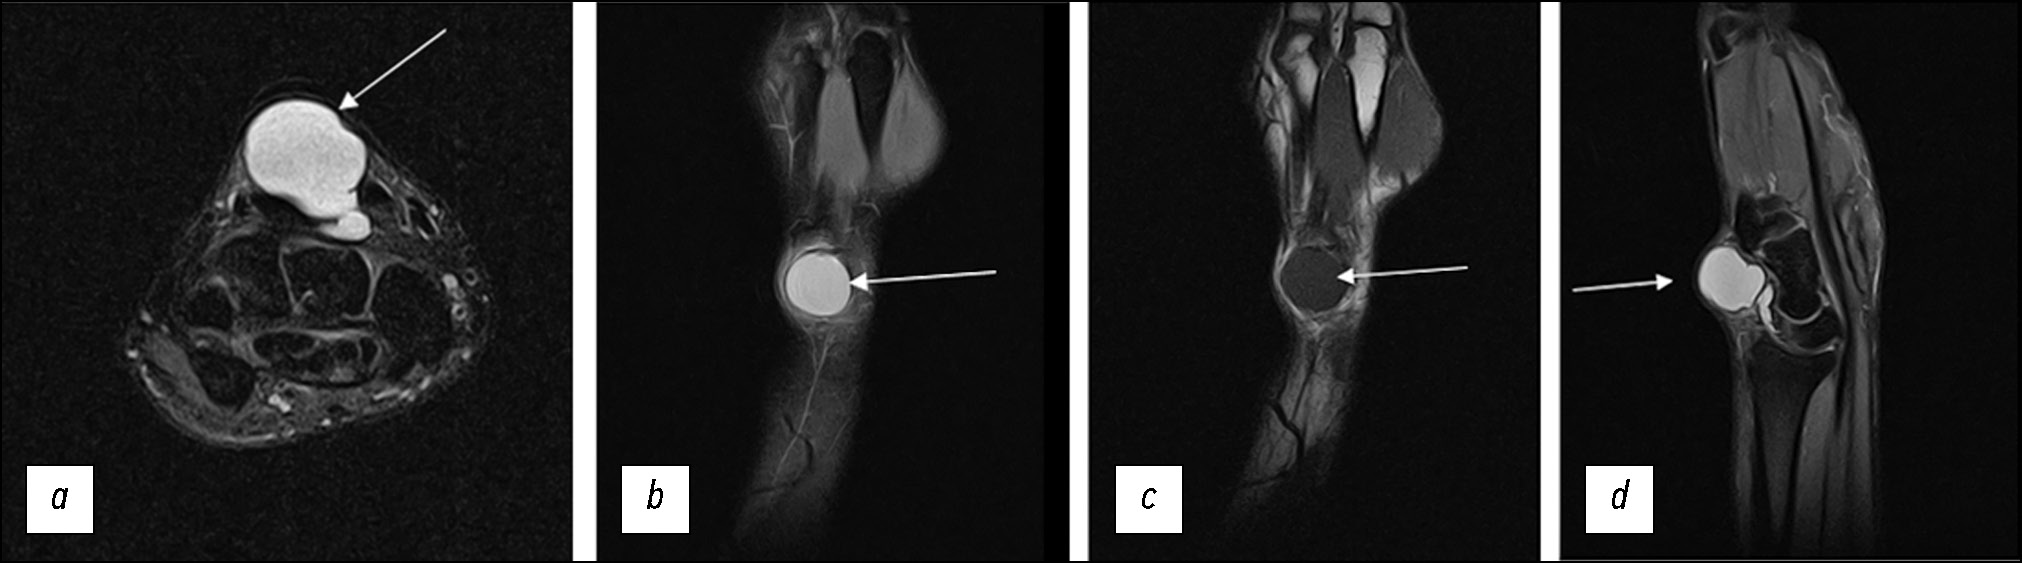

The limitations of the proposed fixation method include the potential inability to use the described splint in patients with contractures or large-space-occupying masses resulting in gross deformation of the contours (Fig. 6). However, in this case, the remaining recommendations should be followed regardless.

Fig. 6. Large encapsulated ganglion cyst of the dorsal hand with neck-like connection to the wrist cavity; (a) PD-weighted images with fat suppression in the axial plane; (b) PD-weighted images with fat suppression in the coronal plane; (c) T1-weighted images in the coronal plane; (d) PD-weighted images with fat suppression in the sagittal plane.